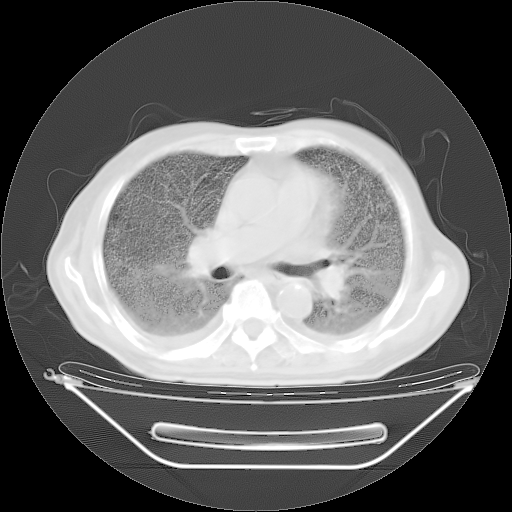

今天复查肺部CT,发现双肺广泛磨玻璃样改变。所以我把3月19日和5月9日相隔50天的肺部CT上传。请大家会诊。

5月9日肺部CT(在4月27日齐鲁医院肺部CT描述部分肺组织磨玻璃样改变,12天后肺组织广泛磨玻璃样改变)

2009年5月9日肺部CT

大致读了系列胸部CT:纵隔窗无明显异常,肺窗:从4、27至今:主要是双肺中下野外带可见毛玻璃样改变,目前处于急性肺泡炎阶段,至于原因考虑1、结替组织或胶原血管性疾病所致?2、恶性疾病如恶组在肺部所致的表现或细支气管肺泡癌?3、药物或其它原因如肺蛋白沉着症所致肺泡炎目前不太可能?总之,明天就去请我院的呼吸科、感染科、血液科和临免专家会诊哈。